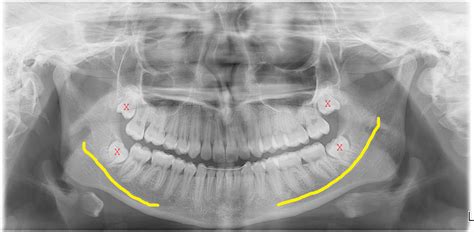

Comme on peut le voir sur le croquis, le nerf dentaire inférieur, qu'on appelle maintenant nerf mandibulaire ou aussi nerf alvéolaire inférieur, passe très près des racines des molaires et il peut être endommagé lors de l'extraction d'une molaire, et à plus forte raison lors de celle d'une dent de sagesse incluse surtout ci celle-ci fait un crochet qui passe en dessous du canal. Comme on peut le voir sur le croquis, le nerf dentaire inférieur, qu'on appelle maintenant nerf mandibulaire ou aussi nerf alvéolaire inférieur, passe très près des racines des molaires et il peut être endommagé lors de l'extraction d'une molaire, et à plus forte raison lors de celle d'une dent de sagesse incluse surtout ci celle-ci fait un crochet qui passe en dessous du canal. Il est primordial de porter une attention particulière à toute douleur persistante ou aiguë se manifestant au niveau de vos dents de sagesse

Clinique Spécialisée de Québec Dents de sagesses. Les dents de sagesse, dernières molaires à apparaître dans la bouche, peuvent causer des problèmes, notamment en touchant le nerf mandibulaire Le nerf mandibulaire se divise en plusieurs branches, dont le nerf alvéolaire inférieur.